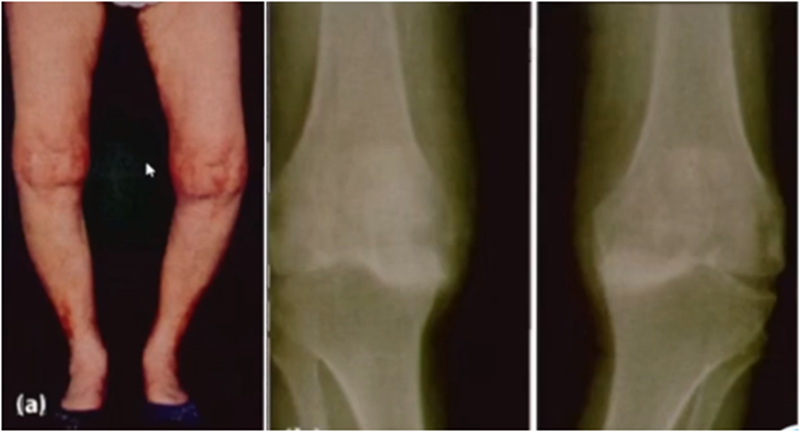

侧位片可以显示胫骨平台磨损部位,在判断前交叉韧带功能是否完好方面有重要意义。当磨损部位在前方或中前方,没有延伸到胫骨平台后缘时,说明前交叉韧带功能正常;当磨损部位延伸到胫骨平台后方,甚至引起后方半脱位状态时,说明前交叉韧带功能缺失或损害,此时不适合做单髁。

查体特点:屈曲位畸形消失

后方软骨完好,恢复关节间隙,恢复MCL张力

AMOA的侧位X线表现

ACL功能完好是单髁重要的适应证。当ACL失去功能,导致后方软骨磨损或者骨缺损,此时为整个内侧或全间室的骨关节炎,不是单髁的适应证了。

在牛津单髁标准教程里,表明前交叉韧带与后交叉韧带都应该保持功能正常,才是单髁的适应证。